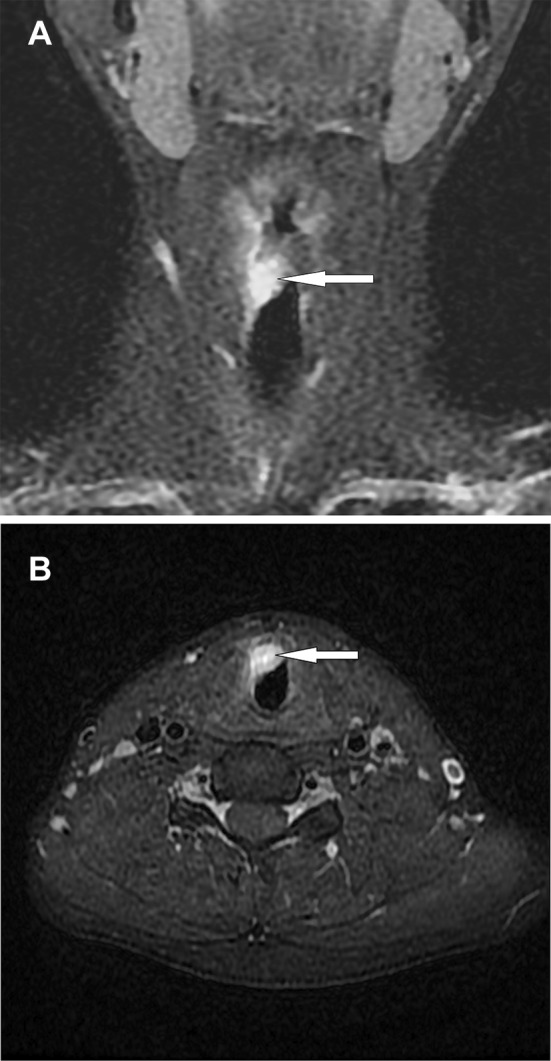

A 23-year-old male smoker was admitted to hospital for a progressive aphonia of 4 months duration and chronic laryngitis unresolved by corticosteroid treatment. There was no history of fever or weight loss and no cervical lymphadenopathy. Laryngoscopic examination revealed a small, non-ulcerated, red, subepithelial, polypoid mass arising from the right vocal cord and extending to the anterior commissure. The computed tomography (CT) imaging demonstrated heterogeneous enhancement of a nodular mass within the glottic and subglottic plane. It was lateralized to the right and measured 14 × 13 mm in size (Fig. 1a, b).

Fig. 1.

a Coronal fat saturation T1-weighted post contrast MRI shows thickening of the right true vocal fold (arrow). b MRI axial scan shows a soft tissue mass arising from the right vocal cord (arrow)